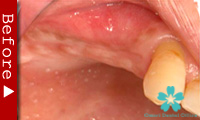

歯を一本だけ失った場合

“失われた1本の歯根の代理品”としてインプラントを1本だけ使って失った歯の部分を修復する方法は、最も洗練された治療方法であり、審美的にも満足のいく結果が得られます。

1本のインプラントによってあたかも自分の天然歯のように自然に感じられます。顎骨の”萎縮”の心配もなく、本来の骨量を維持できます。

ブリッジを入れる時のように、健康な隣の歯を削る必要がありません。